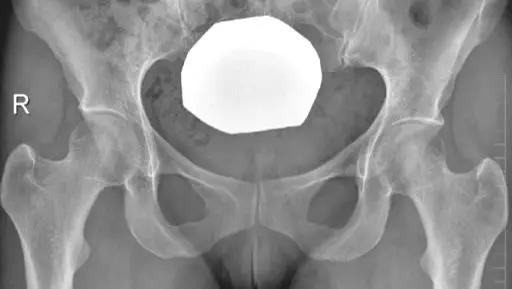

- 正常髋关节X线表现。

- 中心边缘角(LCE角)正常范围为25一39;髋臼指数(AI)正常值>0;挤压指数(E/A+E)正常值<25%。

- IIL:髂坐线;AW:髋臼前壁缘;PW:髋臼后壁缘;A为股骨头被髋臼覆盖部分的宽度;E为股骨头未被髋臼覆盖部分的宽度;F为髋臼窝线。

髋臼过深,髋臼窝线位于髂坐线内侧。

- 髋臼窝线位于髂坐线内侧。

- LCE>39°时,提示髋臼过渡覆盖。

- 正常髋臼指数(AI)为正值,AI为0或负值提示髋臼过深。

- 髋臼过深:髋臼线位于髂坐线内侧。